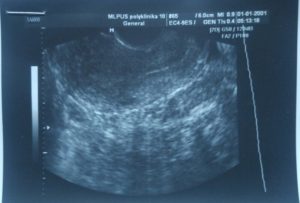

В начальные недели эмбрионального развития рекомендуется проводить трансвагинальное ультразвуковое исследование. Этот метод включает введение узкого датчика во влагалище, что обеспечивает четкое изображение матки на экране. Близость датчика к исследуемой области гарантирует высокое качество изображения. Специальная подготовка не требуется, процедура безопасна и не вызывает осложнений.

С помощью ультразвукового исследования на ранних сроках специалист может обнаружить зародыш на 5-й день после задержки менструации, но только при трансвагинальном обследовании. Специальный датчик позволяет установить наличие оплодотворенной яйцеклетки, ее местоположение и срок развития.

Во время трансвагинального осмотра врач может выявить внематочную имплантацию эмбриона примерно через 10-12 дней после зачатия. Процедура с вагинальным датчиком безопасна, если у беременной нет периодических кровяных выделений или мазков.